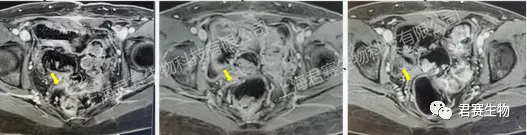

令人欣喜的是,一位曾被确诊为IV期子宫内膜癌的患者L女士,继接受君赛生物GC101 TIL单次回输治疗后2个月,肿瘤病灶即完全消失,获得CR(完全缓解)疗效,至今已无瘤生存超4年,摆脱需长期服药和频繁辗转于各大医院带来的生理和心理上的煎熬,回归正常生活和工作的健康状态。

幸运的是,L女士经朋友介绍得知,君赛生物正在上海市第十人民医院开展GC101 TIL治疗复发/晚期妇科肿瘤的临床试验。在程忠平教授及十院妇科医护团队的密切配合下,L女士于2021年8月顺利接受了TIL细胞回输。出院后每次定期随访结果均显示肿瘤标志物持续降低,肿瘤持续缩小,治疗后两个多月各项检查指标便恢复正常水平。